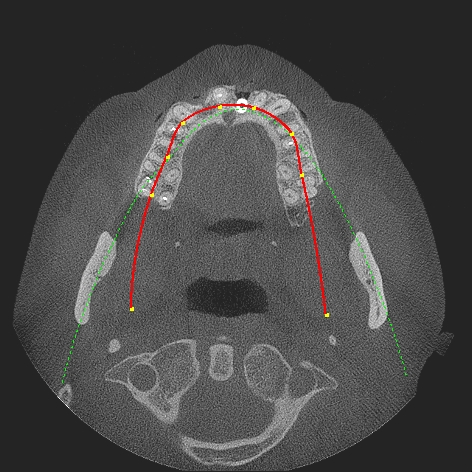

術前術後のCTになります

術後のCTになります

安定した口蓋側の固有骨内にインプラントが入りました